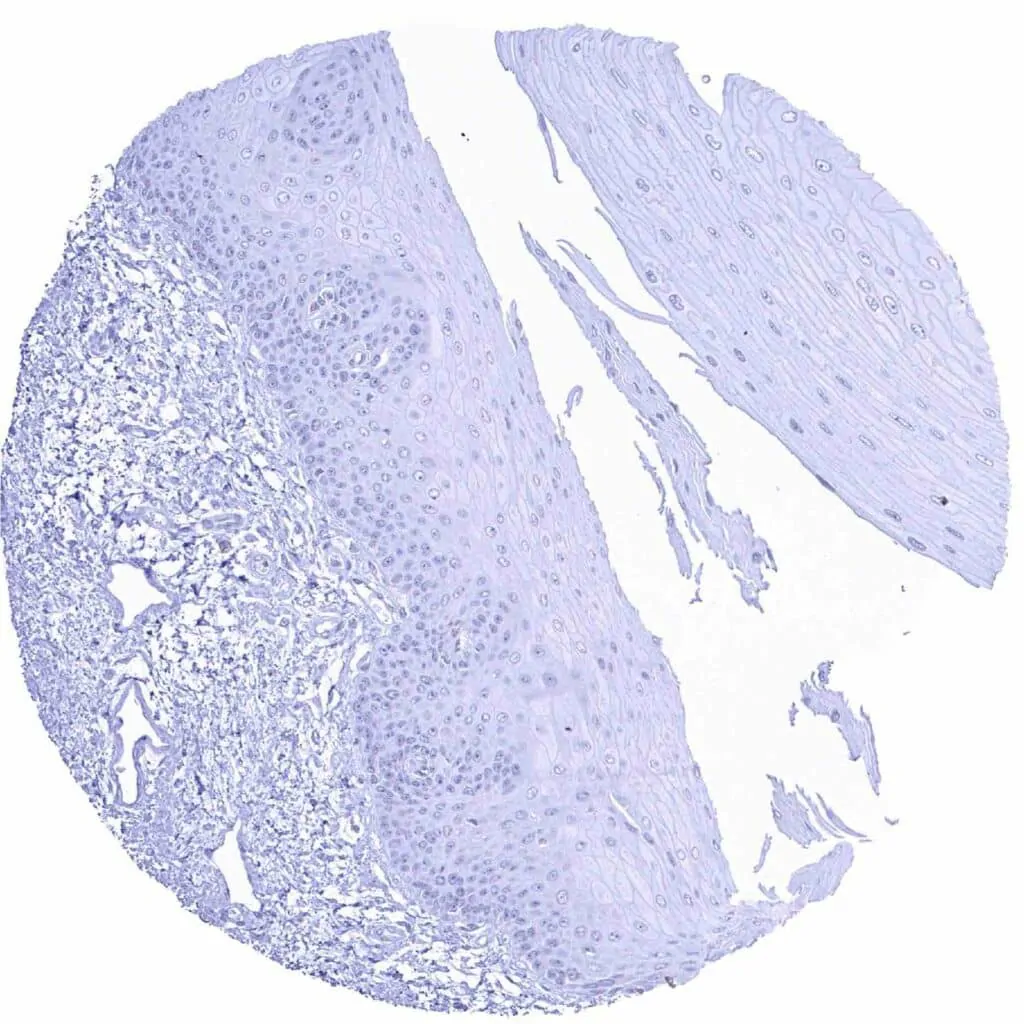

Esophagus, squamous epithelium